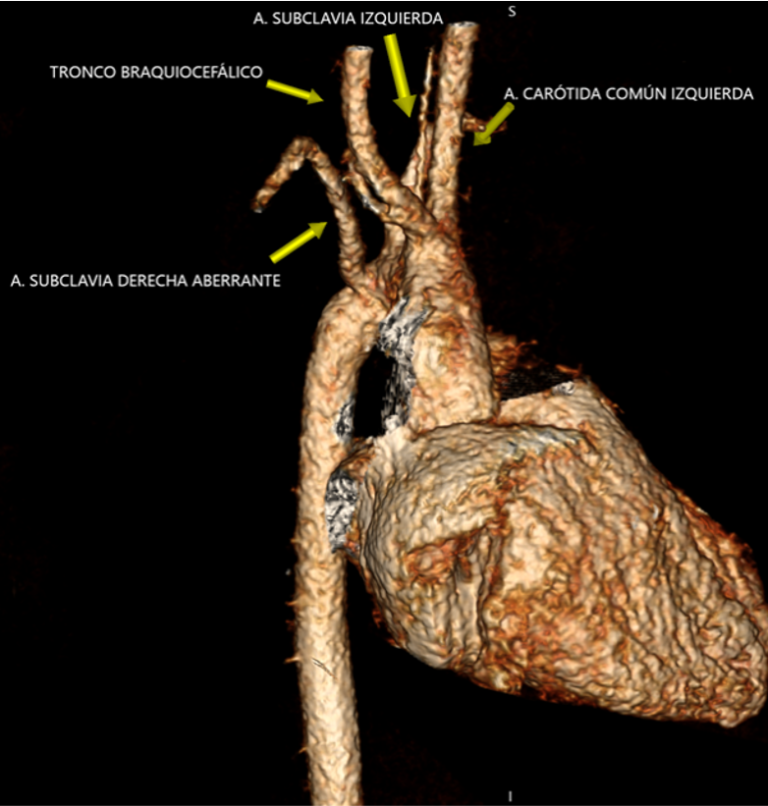

El área de Diagnóstico por imágenes del Hospital Favaloro realizó una angiotomografía de tórax a una paciente pediátrica de tan solo 6 años de edad, donde se visualizó una variante anatómica llamada “arteria subclavia derecha aberrante” con un trayecto retroesofágico generando efecto compresivo del mismo.

Desde el área de Diagnóstico por Imágenes se recibió a una paciente pediátrica, de tan solo 6 años de edad, quien consultó por vómitos de 1 mes de evolución con múltiples consultas en diversos centros de salud y una internación reciente.